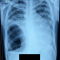

Alo dokter, izin diskusi dok. Pasien anak 3 tahun datang dgn keluhan demam 4 mgg,batuk4 mgg, bb turun tidak ada kontak tbc skrg, kgb tdk membesar, rontgen broncopneumonia infiltrat bertambah terakhir rontgen 1 tahun yg lalu hasil broncopneumonia evaluasi dari pengbtan tbc 6 bulan karena pasien riwayat pengobatan tbc 1 tahun yg lalu 6 bulan tuntas. Izin dok penegakan diagnosis apakah ini tbc relapse atau hanya bronkopneumonia. Karena uji mantoux tdk bsa tegak karena pasien pernah rwyt tbc pasti hasil positif, pemeriksaan apalagi untuk menegakan diagnosis tbc reinfeksi pada anak?